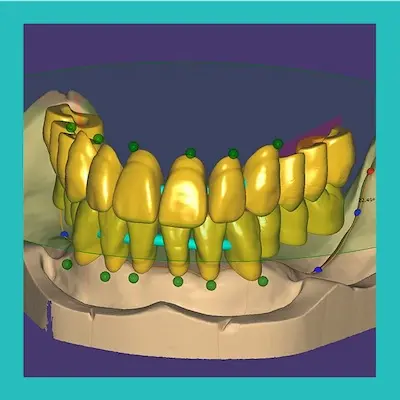

Bilgisayar ortamına aktarılan ağız ölçüleriniz uzman ekibimiz tarafından incelenir ve 3D tedavi planınız çıkartılır. Tüm diş hareketleriniz 3D olarak hekiminize gönderilir. 3D tedavi planını inceleyebilir ve tedaviye başlamadan önce tedavinin sonundaki yeni gülüşünüzü nasıl olacağınızı görebilirsiniz. Tedaviye başlamadan önce tedavi sonundaki halini kim görmek istemez ki?

- Dijital, profesyonel tasarım

- Modern, yüksek teknolojik çözüm.

- Çağın ilerisinde ilerleyen işleyiş ve çözüm

Estetik diş hekimliği denilince akla gelen ilk kavramlardan biri ''gülüş tasarımı''dır. Gülüş tasarımı; çeşitli nedenlerle estetik açıdan görünümü bozulan dişler ve diş etlerinin hastaların yüz şekilleri ve gereksinimleri de göz önünde bulundurularak olabildiğince doğal ve güzel bir görünüme kavuşturulması işlemidir. Multidisipliner bir yaklaşım olan gülüş tasarımı, birçok işlemin bir arada uygulanmasıyla gerçekleştirilmektedir.

Tedavinin ilk aşaması restore edilecek dişin ağızdaki hazırlıklarının yapılması gerekir. Ardından hastanin ağzından optik kamera ile taratılan görüntüler direkt olarak cihaza kayıt edilir ve bilgisayar üzerinde bulunan özel yazılımlar kullanılarak hastaya en uygun protezlerin tasarımı hazırlanır. Bizde en iyisini imal etmek için çalışmaktayız.